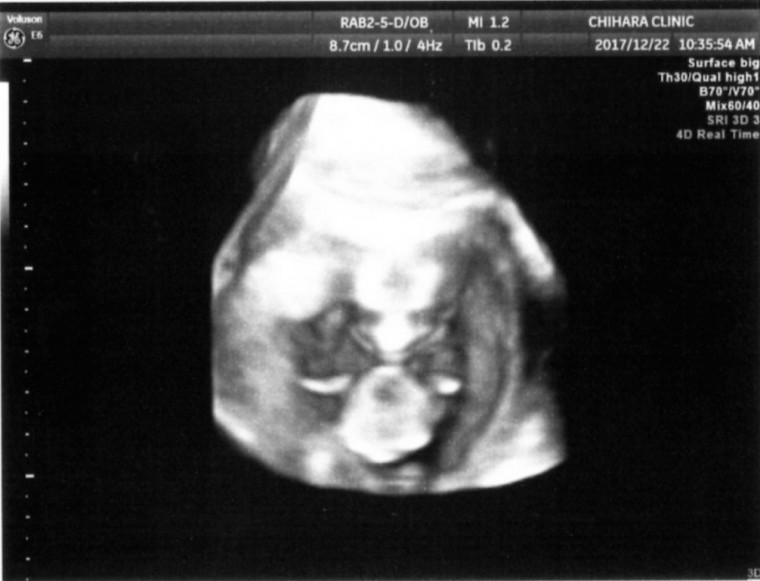

最初はエイリアンに見えたよ笑

妊娠4ヶ月(13週5日)撮影日:2017年12月22日

はじめて人の形で見えた